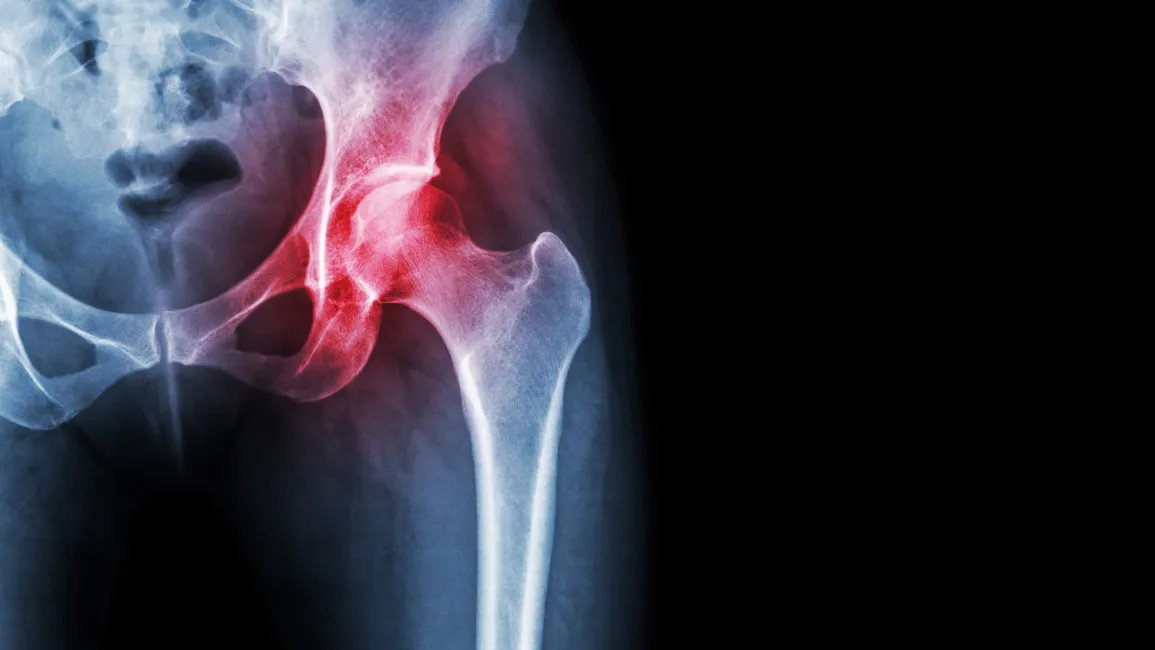

Most cases of hip pain do not start in constant pain – usually, the pain is intermittent and only made worse with certain movements or positions. Initially, the symptoms are often described as a dull, nagging, deep pain that can feel like a sharp catch in the front of the hip. As the hip slowly continues to degenerate through the stages of osteoarthritis, the pain worsens to be painful with most movements.

If the pain does not drive the patient to seek care from their physician, usually that feeling of instability will. If the hip joint shows significant degeneration, the treatments could vary from medication management to injections, physical rehabilitation, or even a total joint replacement surgery. If surgery is a consideration, this is when hip pain sufferers look for alternative treatment options.

Although bursitis and degenerative arthritis are what many associate as the cause of hip pain, there are many other potential causes of hip pain as well. This is what can make the diagnosis problematic in many cases. This can be further complicated by the fact that some patients also have more than one cause contributing to their pain.

Fortunately, most of the common causes of hip pain can be accurately evaluated through physical testing and imaging – including x-rays or an MRI. To obtain the most accurate diagnosis, it is essential to determine if the cause of pain is coming from the actual hip joint, the spine, hip flexor, hip rotator(s), or referred to the hip from another source. Using a practitioner who takes an integrated approach is wise, as they are more likely to recommend a comprehensive approach and provide alternatives to total hip joint replacement surgery whenever possible.